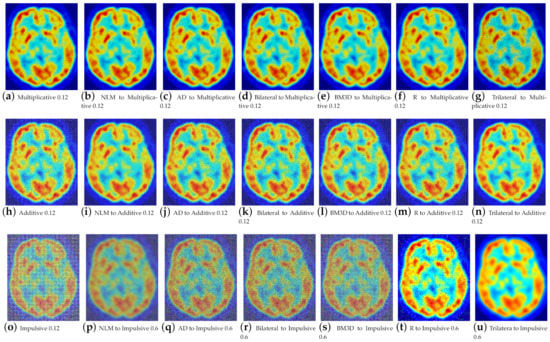

5. Experimentation and Results

5.1. Standard and Medical Grayscale Image Processing